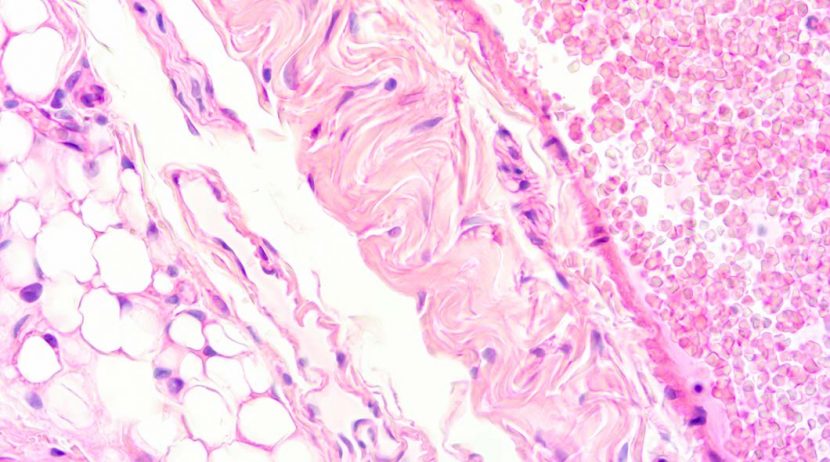

Cardiomiopatia ou miocardiopatia: têm o mesmo significado. É um termo genérico para doenças do músculo cardíaco, em que as paredes das cavidades do coração ficam esticadas, espessas ou rijas. Estas alterações afectam a capacidade do coração para bombear sangue para o corpo.

Quer prefira dizer cardiomiopatia ou miocardiopatia, a maior parte delas são genéticas e reconhecidas desde a infância. No entanto, algumas podem desenvolver-se mais tarde. Deixamos-lhe aqui algumas das mais reconhecidas atualmente: a dilatada, a hipertrófica e a restritiva.

Cardiomiopatia dilatada

As paredes do coração ficam esticadas e finas e por isso o coração não consegue contrair da mesma forma. Pode acontecer em crianças e adultos.Com esta doença há o risco alto de insuficiência cardíaca. Os sintomas típicos são:

Cardiomiopatia hipertrófica

Nesta patologia, as paredes coração ficam mais espessas, fazendo com que as cavidades (aurículas e ventrículos) sejam mais pequenas. Assim sendo, não consegue entrar tanto sangue para as mesmas e é mais difícil que relaxem. Pode levar a alterações nas válvulas do coração e uma obstrução no movimento do sangue.

Cardiomiopatia restritiva

Caridomopatia restritiva é uma doença rara, normalmente diagnosticada na infância. As paredes do coração ficam rijas, não permitindo um relaxamento das cavidades, consequentemente não entrando sangue até encher. Pode levar a insuficiência cardíaca e alterações nos batimentos cardíacos.